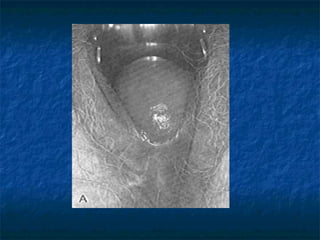

Uterine prolapse

n  First degree:

descend below ischial spine not reach

introits

n  Second degree :

cervix visible at introits

n  Third degree:

procidentia

the whole uterus is out side the introits